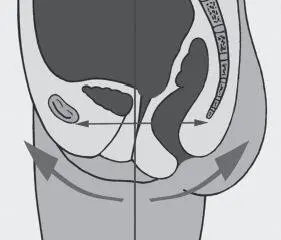

Все отклонения в положении таза: высокое или низкое положение копчика, смещение лобковой кости в результате травм и пр. (Рис. 3–4), перерастягивают мышцы тазового дна, либо, напротив, лишают их опоры, в результате чего они провисают растянутым гамаком. Эти отклонения фасциально передаются по телу, заставляя его искажаться и искать пути компенсации для сохранения вертикального положения.

Рис. 3. Отклонение таза вперед, копчик выше нормы

Рис. 4. Отклонение таза назад, копчик опущен

В результате всегда формируются места мышечного перенапряжения, мягкие ткани начинают смещаться, формируя обвислости и блоки.

Это нарушает ток энергетических потоков и приводит к таким проблемам, как опущение внутренних органов (спланхоптоз), застойные и воспалительные явления в органах малого таза, искажение скелетной части и смещение мягких тканей тела.